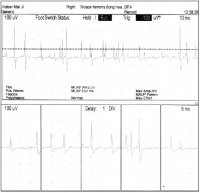

神经性肌强直右侧股二头肌肌电图

神经性肌强直的病因机制一直在探讨中。目前认为此病属钾通道异常而致的钾通道病中的一种具有高度普遍性和多样性的钾通道,是控制膜的去极化细胞奋性的基础钾通道病的一个普遍特征是膜电位复极化的减弱 Kleman等认为神经性肌强直与慢钾通道传导的调节有关,它导致刺激后神经轴索兴奋阚值降低,去极化或超极化兴奋性过度,持续时间延长面产生异常电活动,引起连续的运动单位括动=自发电括动的部位大多位于神经终束运动终板或运动轴索末梢分叉处,也可沿轴索全部或产生于运动轴索的某些近端区域的血一神经屏障内,甚至可累及前角运动细胞本身 。这种离子通道变化导致的运动轴索的过度兴奋,使受累肌肉出现颤搐、僵硬。肌电图所见高频自发性运动单位放电活动及成对的或多源的运动单位发放是神经性肌强直和肌纤维颤搐的特征性表现,提示了运动轴索的兴奋性特点:活检病理中可见少数肌纤维轻度萎缩,表明率病有周围神经损害。

本病的诊断主要依据为 :① 多在20岁左右起病,男性多见,少数有家族遗传史。② 临床特点为始自肢体远端的持续性肌纤维颤搐.明显时肌纤维收缩渡沿肌纤维纵轴方向呈波浪样前进,可伴肌松弛困难;运动后出现痛性肌僵硬.常伴过度出汗,休息后可缓解.睡眠时肌痉挛不消失③多为全身性可累及躯干、四肢肌肉,手足、面肌、跟睑肌、腹肌等亦可受累④ 可见肌肥大或萎缩,腱反射可因肌强直而减低或消失.无扣击性肌强直。⑤ 肌电图表现为自发持续性的运动单位放电活动。⑥苯妥因钠或卡马西平治疗效果良好。

神经性肌强直的主要表现为受累肌肉出现肌僵硬、痉挛、颤搐、无力和肌弛缓延迟,肌电图检出自发性持续性的运动单位放电活动。在休息状态下仍表现活跃的运动神经元电位,通常只有神经性肌强直和stiff-man综合征。